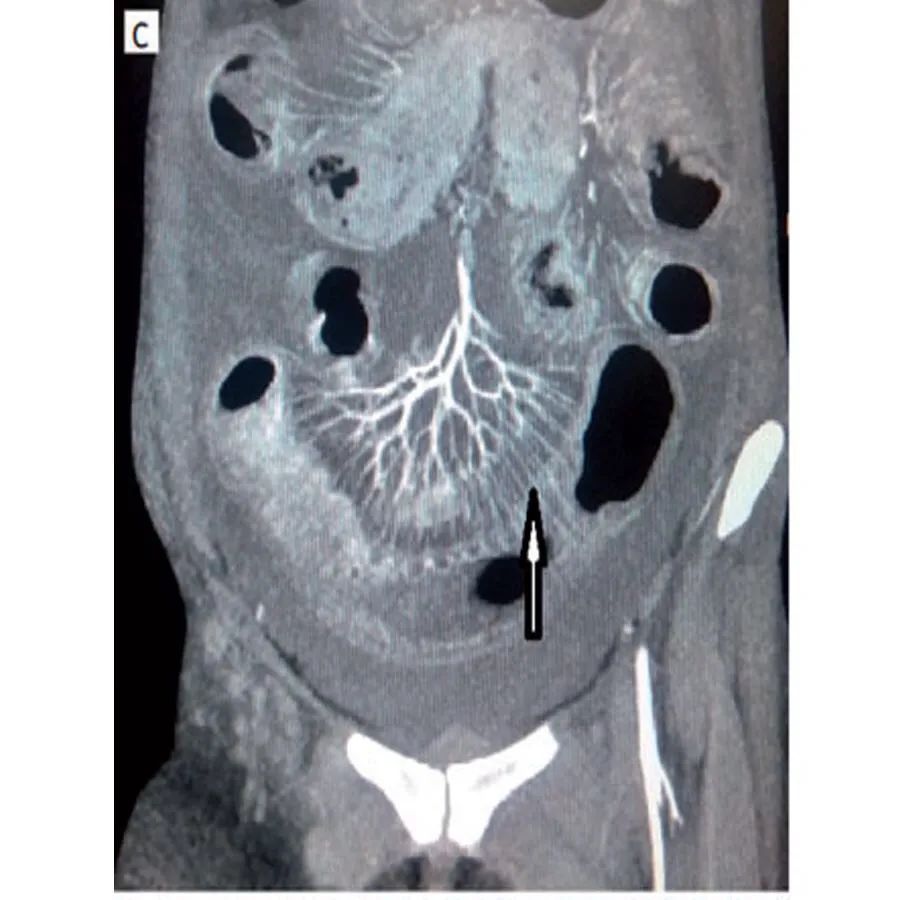

腹部血管CT血管造影梳状征提示肠系膜血管炎(图1C)。

腹部CT下正常人的肠管壁厚度不超过3mm,大于等于4mm则被认为肠管壁异常增厚。常见的CT表现包括肠壁局部或弥漫性增厚,肠壁异常强化,肠管呈梳状排列(梳状征),腹水及肠壁肿大。肠壁增厚通常是多灶性的,不局限于单个血管领域,因为肠系膜血管炎可能同时影响多条血管。增强CT(CTA)扫描清晰显示肠壁和腹部血管,提髙诊断的准确性。腹部增强CT肠管异常可表现为受累增厚肠段的黏膜层和浆膜层出现明显强化,而中间的肌肉层强化较低,犹如一个靶子,故称为“靶形征”或“双晕征”。肠系膜异常表现为肠系膜的血管增粗、增多,异常排列如“梳状”或“栅栏状这是系统性红斑狼疮合并肠系膜血管炎的常见征象。但需要注意的是,机械性肠梗阻,急性胰腺炎等也可引起肠管扩张,肠壁水肿增厚等变化,因此腹部B超,腹部站立位平片,腹部CT不仅可以帮助诊断,同时对于鉴别诊断也非常重要。与普通CT相比,肠道血管CT造影是诊断系统性红斑狼疮合并肠系膜血管炎的金标准,特别是当患者出现肠缺血、血栓等血管炎表现时,CT造影显示肠道节段性改变,正常肠道和异常肠段交替出现,呈多灶性的特征。